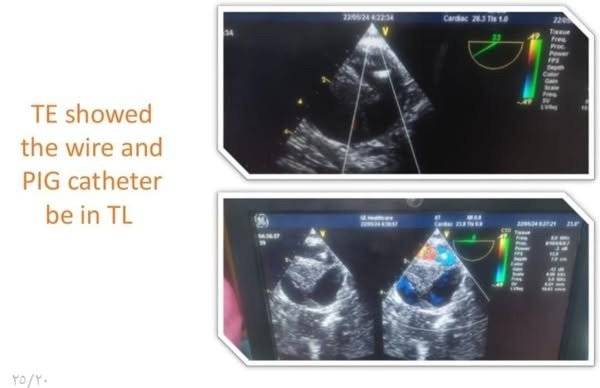

وتابع البيان، بناءً على التقييم الطبي للحالة تقرر إجراء تدخل مزدوج حيث تضمنت المرحلة الأولى إجراء عملية قلب مفتوح لاستبدال الشريان الأورطي الصاعد وإعادة توصيل شرايين الرقبة باستخدام شرايين صناعية، فيما شملت المرحلة الثانية تركيب دعامات مغطاة بالشريان الأورطي وقوسه باستخدام تقنية TEVAR وغلق الشريان تحت الترقوة باستخدام سدادة عبر القسطرة التداخلية تحت توجيه الأشعة التلفزيونية عن طريق المريء وتم تنفيذ التدخلين باستخدام أحدث التقنيات الطبية وبكفاءة عالية أسفرت عن تحسن ملحوظ في حالة المريض الذي غادر المستشفى بعد أسبوع من المتابعة الدقيقة وهو بحالة مستقرة الآن.